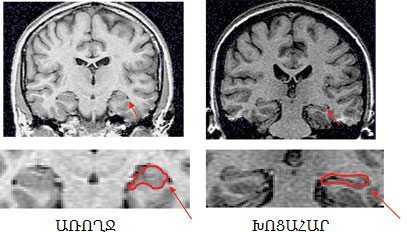

Ժամանակակից արհեստագիտութիւնը կ’օգնէ, որ հոգեբուժութիւնը դառնայ աւելի ճշգրիտ գիտութիւն: Այսօր կարելի է ուղեղի կառոյցը եւ աշխատանքը «տեսնել» երեք տարածաչափային (3 տի.) պատկերներով` շնորհիւ մագնիսական համահնչութեան (MRI) եւ այլ միջոցներու: Օրինակի համար, որեւէ տուեալ պահու ուղեղի աւելի գործօն մասերը աւելի մեծ կարիք ունին արեան: Այդ կարելի է չափել:

Կողքի նկարին մէջ սլաքը ցոյց կու տայ ուղեղի այն մասը, որ կը վերաբերի յիշողութեան (hippocampus): Չափագրութիւնները ցոյց տուած են, որ հոգեկան խոցը կը խախտէ հորմոնի հաւասարակշռութիւնը, կը կծկէ hippocampus-ը ուրեմն եւ կը խանգարէ յիշողութեան գործողութիւնը: Քովի նկարը ցոյց կու տայ, որ խոցահար ուղեղի տուեալ մասը ակնյայտօրէն խեղուած է: Նկարը առնուած է աղբիւրէ մը, որ այս մարզին մէջ դասագիրքի կարգ անցած է (3): Հարկ է այստեղ նշել, որ հոգեկան ճնշումն ու խոցը կ’այլակերպեն նաեւ ուղեղի այլ մարզերը: